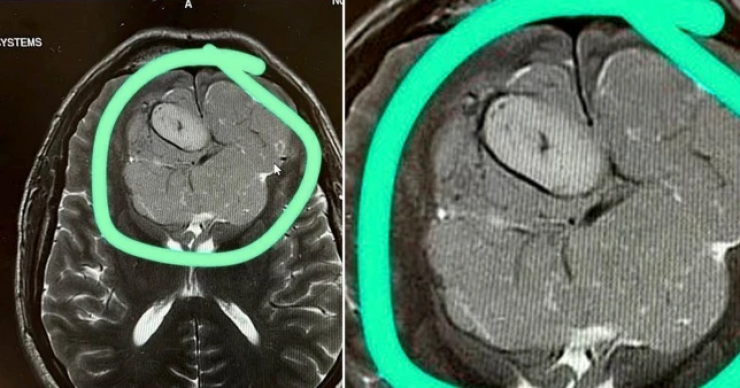

На следующий день специалисты с помощью МРТ выяснили, что зрение у мужчины упало из-за большой опухоли. Новообразование давило на мозг.